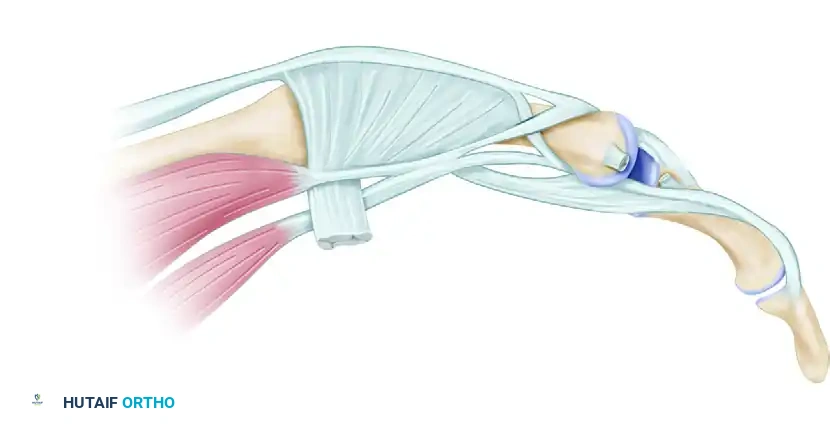

Similarly, volar dislocations can present with complex pathoanatomy, often suggestive of a central slip injury. In severe cases, the radial condyle of the proximal phalanx may buttonhole through the extensor mechanism, trapping the lateral band volarly.

Volar dislocation of the middle finger PIP joint, suggestive of a central slip injury.

Proximal phalangeal radial condyle buttonholed through the extensor mechanism with the lateral band trapped volarly.